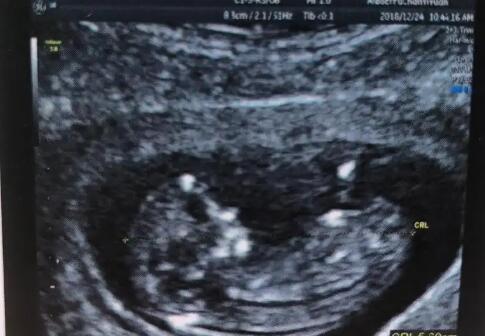

怀孕前57kg ,现在体重59kg 因为体重没怎么涨,肚子也不是很明显。担心宝宝的营养跟不上,医生说不用看肚子大小,B超显示宝宝现在体重550g 而且吸收的很好,我就放心了

我今天看到宝宝的小JJ啦,医生也说是个小王子。